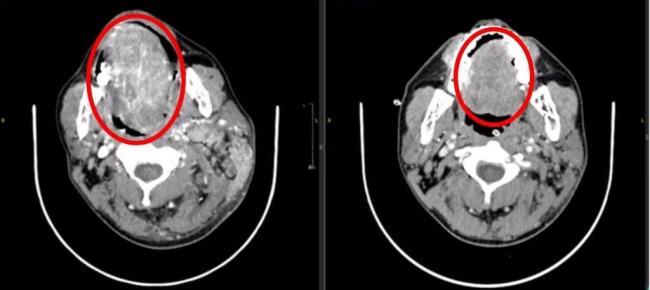

上海第九东谈主民病院口腔颌面-头颈肿瘤科接诊了这名33岁的患者。从发现舌头左侧有溃疡到来病院看病,前后仅2个多月时分。此时,患者的口腔溃疡不仅莫得愈合,反而赶快发展,彭胀到了悉数这个词舌头再到下颌,不仅舌头动不了,嘴巴也张不开,吃东西费事。肿瘤还从舌头搬动到了颈部,径直包住了左侧颈动脉,属于晚期高危病东谈主。

经由两个月的药物治愈,星空体育患者肿瘤彰着减弱后,手术施伸开展。在麻醉科、病理科、养分科、影像科等多学科大家的匡助下,手术历经10多个小时,患者顺利继承了左舌颌双颈纠合根治术,同时还完成了自体组织移植,进行舌和颈部设置手术。手术中切掉了4/5的舌头,并取患者大腿外侧皮肤肌肉血管组织进行修补,以减少术后并发症的风险。